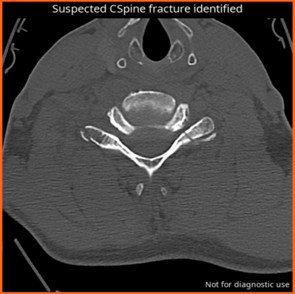

CINA-CSpine

Avicenna

Automatic detection of intracranial hemorrhages (ICH) and cervical spine fracture (CSpine) on Non Contrast CT.